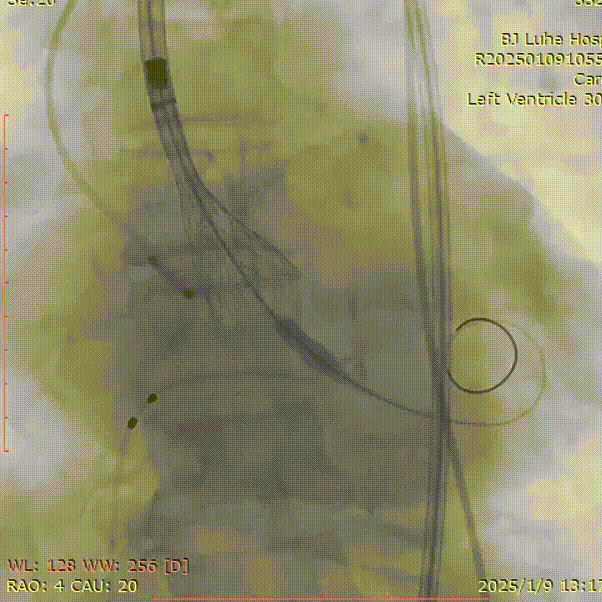

术中影像

调整植入深度

最终造影

术后下肢动脉造影

最终植入深度约10mm,少+瓣周漏,造影检查股动脉入路,血管未见损伤,手术顺利结束。